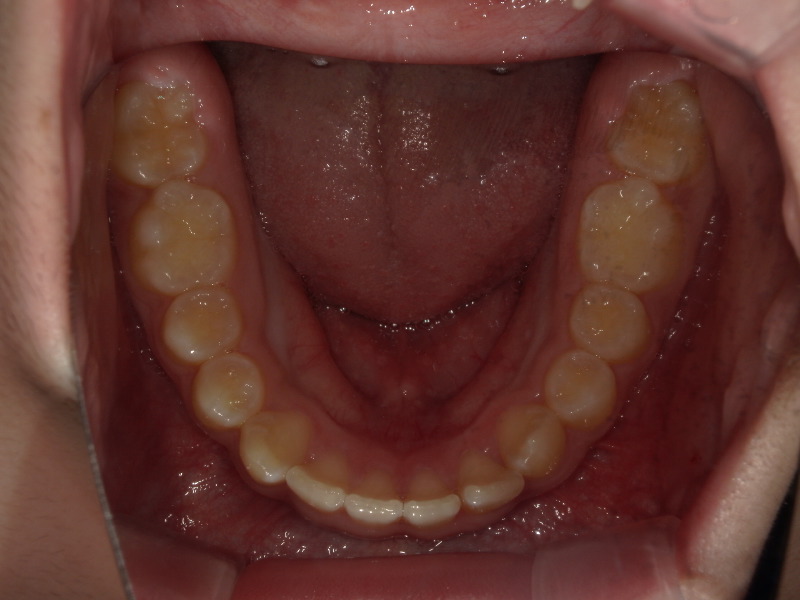

下の歯並び

噛み合わせが深かったのが前にくる=下顎は前に成長しています。

そのため、顎の位置変化が起き、下の顎のアーチは大きくなり、がたつきも改善していきます。

こちらも一年半の経過です。

既に永久歯列なことと、一番奥の親知らずの手前まで歯が出てきていますが、綺麗に入ってきています。